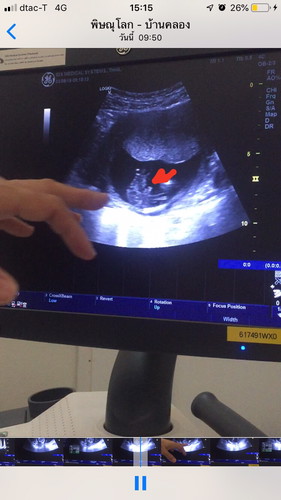

ซาวด์ 15 สัปดาห์ แม่ท่านไหนเห็นเพศลูกแล้วบ้างค่ะ

อยากสอบถามว่าพอดีคุณหมอแจ้งว่าน้องเป็นเพศชาย90% ไม่ทราบว่ามีแม่ท่านไหนเห็นเพศแบบนี้แล้ว ตอนคลอดผลพลิกแพลงไหมค่ะ ขอบคุณคะ

อันนี้แอบชัดค่ะแม่ น่าจะชัวร์แล้วจ้า